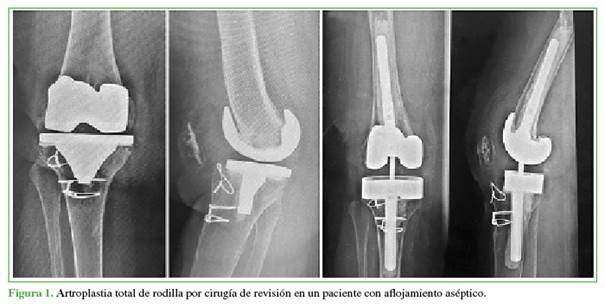

No se hallaron diferencias estadísticamente significativas en la cirugía (primaria o revisión) y el tiempo de seguimiento entre los subgrupos (Figuras 1 y 2).